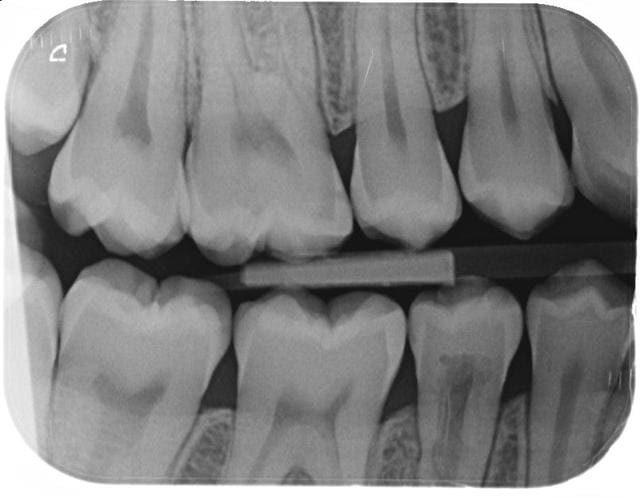

Ci joint btw pre et post orthodontie.

Au niveau de la 45, cela sent la resorption interne. Quel est le mecanisme? Quel traitement? Est ce l orthodontie qui a provoque cette resorption?

ps: il s est ecoule 2 ans entre les 2 radios. Merci pour vos informations.